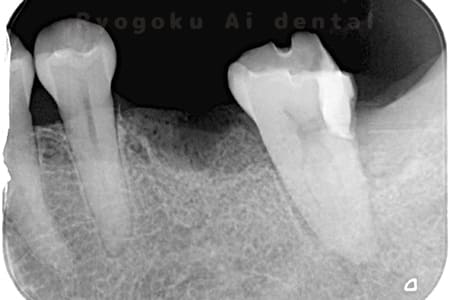

Case02

- 原因

- 慢性根尖性歯周炎

- 治療期間

- 3ヶ月

- 治療内容

- マイクロエンド

- 治療費用

- 121,000円

噛むと痛みが出る、とのことで来院した患者様です。他院での根管治療を終えてましたが、根尖病変を認めるため、マイクロエンドを行いました。

<リスク・副作用>

術後は痛み、腫れ、痺れなどの副作用が生じる場合があります。症状が再発する可能性があります。